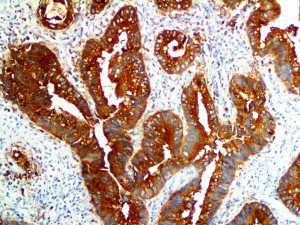

This activation induces inflammatory monocytes to highly express IL-6, starting a localized and then systemic cascade effect that results in hyperproduction of IL-6, which accelerates the inflammatory process. Because IL-6 also increases vascular permeability, excessive levels cause blood vessels to become very leaky. This, along with clotting factors released from vascular endothelial cells, stimulates the coagulation cascade, resulting in microthrombosis (tiny clots), which leads to ischemia and tissue death of the kidney, intestines, heart, liver, brain and extremities.